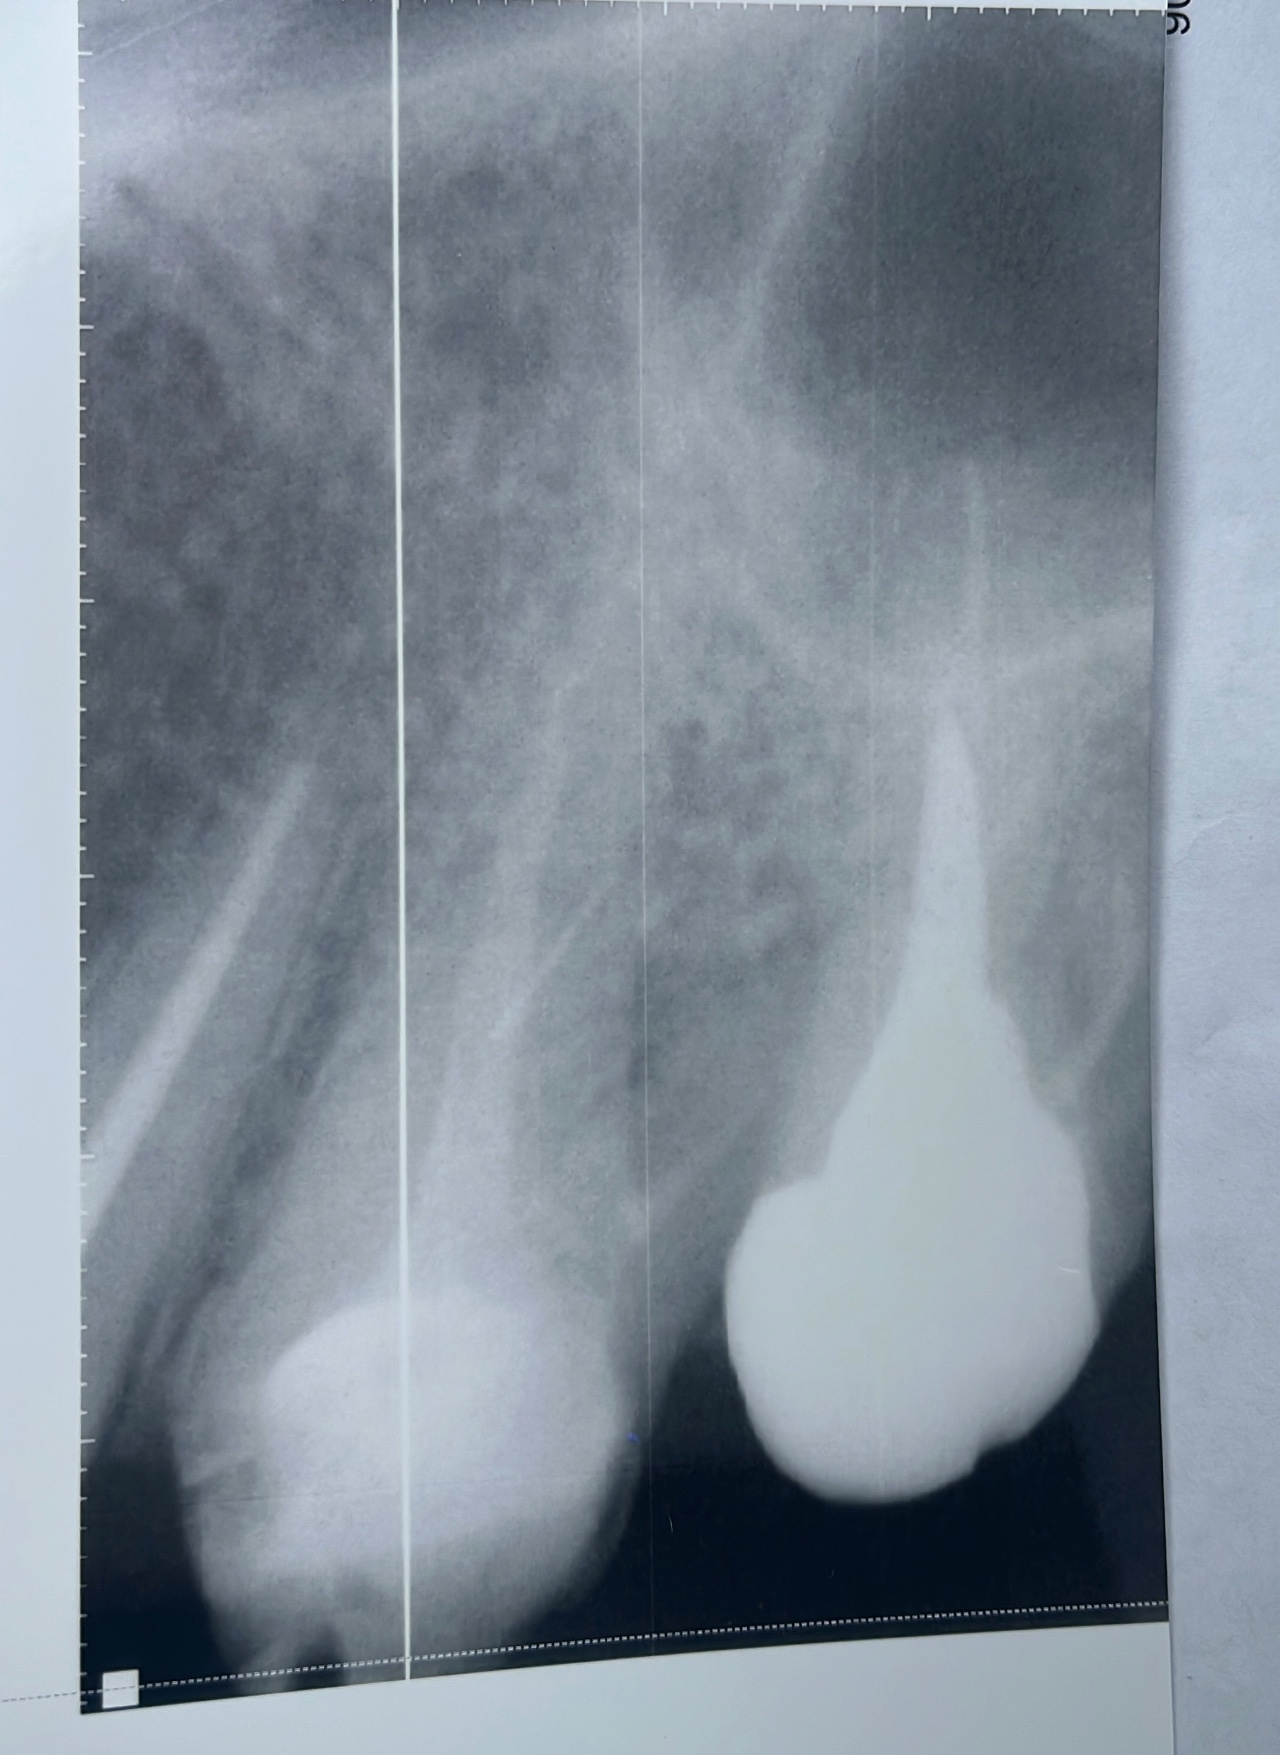

Здравствуйте, несколько мес. Во рту кисло соленый привкус, 26,27 зуб стояли 2 коронки, сняла обе коронки под 26 зуб начал портиться, а 27 установлен 3 мес назад. Но соленый вкус так и идет, сказали парод. Карман. Пока хожу с врем коронкой, есть ли смысл устанавливать постоянные, хотят предложить двойную коронку? У парод была, куэртач делать бесполезно карман будет всю жизнь сказал. Неужели все так безнадежно?